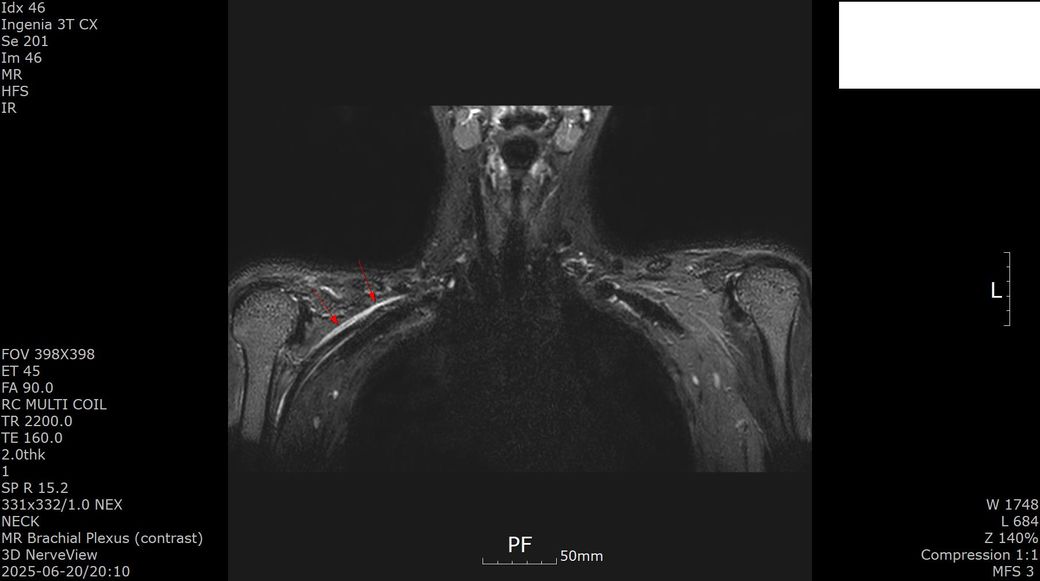

[상완신경총 brachial plexus] mri 판독 부탁드립니다

2025년 1월경 흉곽출구증후군(우측 사각근 유리술, 우측 제1늑골 제거술, 우측 상완신경총 박리술) 수술한 뒤 5개월 지난 2025년 6월경 상완신경총 mri 검사했습니다.

수술 후 발생한 증상과 mri 소견은 상완신경총 손상 또는 신경 재생 지연에 따른 합병증으로 보입니다.

이두근 위축과 근력 저하는 신경 기능 회복이 아직 진행 중임을 시사하고 감각 이상과 손가락 움직임 제한도 신경 손상의 영향일 수 있습니다. 치료는 신경재활치료, 물리치료, 근력 강화 운동과 함께 신경 재생을 돕는 약물치료가 필요하고 상태에 따라 추가 신경 수술이나 재활적 중재가 고려될 수 있습니다!